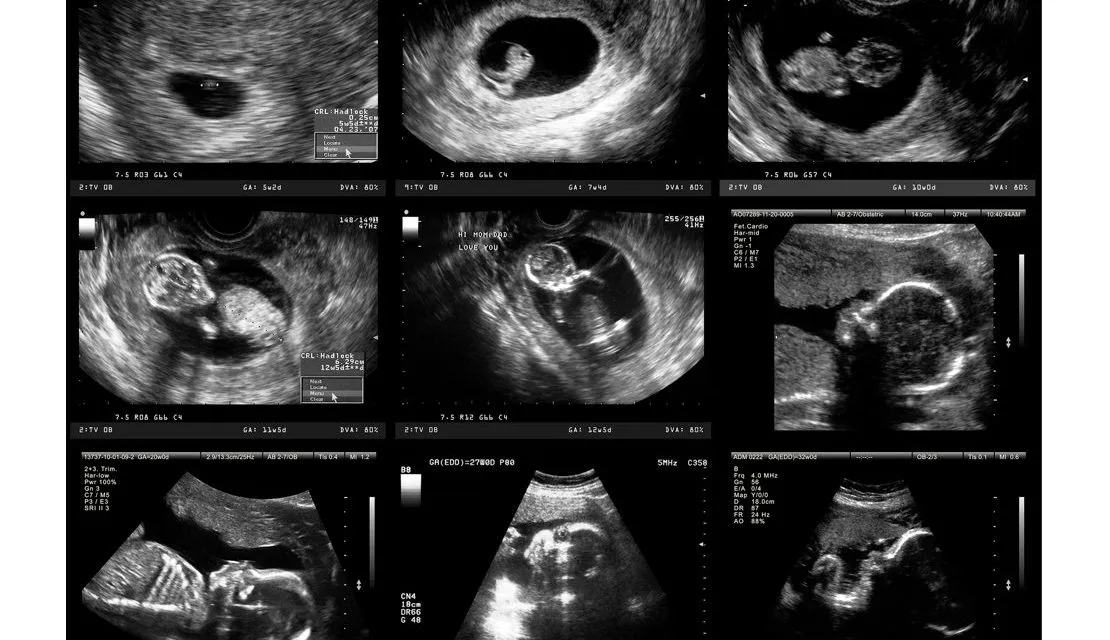

Perkhidmatan Ultrasound

Kami menawarkan pengimejan ultrasound beresolusi tinggi untuk penilaian terperinci organ dalaman dan perkembangan janin, termasuk:

- Ultrasound Abdomen – Pemeriksaan hati, pundi hempedu, pankreas, limpa, buah pinggang dan aorta abdomen.

- Ultrasound Pelvis – Penilaian rahim, ovari, pundi kencing dan prostat.

- Imbasan Antenatal – Imbasan rutin untuk memantau kesihatan janin semasa kehamilan.

- Antenatal Doppler – Penilaian aliran darah janin untuk wanita hamil berisiko tinggi.

- Ultrasound 3D/4D – Pengimejan real time untuk melihat ciri dan pergerakan janin dengan lebih terperinci.

- Imbasan Transvaginal – Pengimejan terperinci organ pelvis wanita.

- Ultrasound Tiroid – Penilaian terperinci kesihatan kelenjar tiroid.

- Ultrasound Payudara – Saringan dan penilaian ketulan atau pertumbuhan yang tidak normal pada payudara.

- Ultrasound Skrotum – Penilaian testis dan skrotum.

- Ultrasound Doppler – Analisis aliran darah dalam arteri dan vena untuk penilaian vaskular yang tepat.